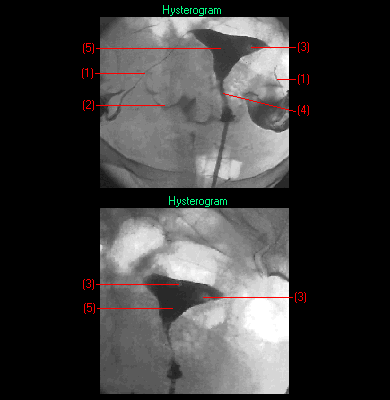

| hysterography | term type: main entry term part of speech: noun number: singular reliability code: 10 definition: X ray examination of the uterus after the administration of a contrast medium. This is a diagnostic procedure for endometrial cancer. (en) check date: 10/08/2001context (x): i_hysgrp.txt origination date: 27/05/2002 |

| histerografía | term type: main entry term part of speech: noun gender: feminine number: singular reliability code: 10 definition: técnica radiográfica que consiste en la opacificación de la cavidad uterina mediante la introducción de un medio de contraste a través del orificio cervical, obteniendo imágenes con fines diagnósticos (p. ej. la detección del cáncer de útero). (es) context (x): e_higrf.txt origination date: 21/05/2002 |